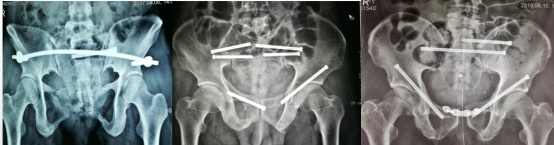

近年,刘华水主任团队较早引进国际先进的第三代通用型骨科手术机器人并成立了首批全国应用示范基地,采用机器人辅助结合骨盆环微创治疗技术,以骨盆环损伤为核心,开展骨盆环微创重建的临床研究,针对部分Tile B型、C型骨盆环多发损伤,大部分病例可以全部以微创手术治疗骨盆环的损伤,避免因切开复位带来的创伤及风险。在论文《骨科机器人微创治疗骨盆环多发损伤》中,回顾性分析因骨盆环多发损伤接受机器人辅助微创手术治疗79例患者,根据损伤不同部位、不同损伤严重程度,在机器人辅助下,所有患者依病情采用INFIX、前环螺钉、LC-II螺钉等内固定微创治疗,微创手术治疗不稳定型骨盆环多发损伤。术后随访表明,在骨科手术机器人的辅助下,与传统手术相比机器人手术操作简单,能保证螺钉置入位置优良的前提下,显著减少X线累积透视次数。在早期手术、螺钉位置、出血量、透视次数、手术时间、骨盆功能、术后并发症、早期活动等方面,治疗效果好,较常规开放手术优势明显。